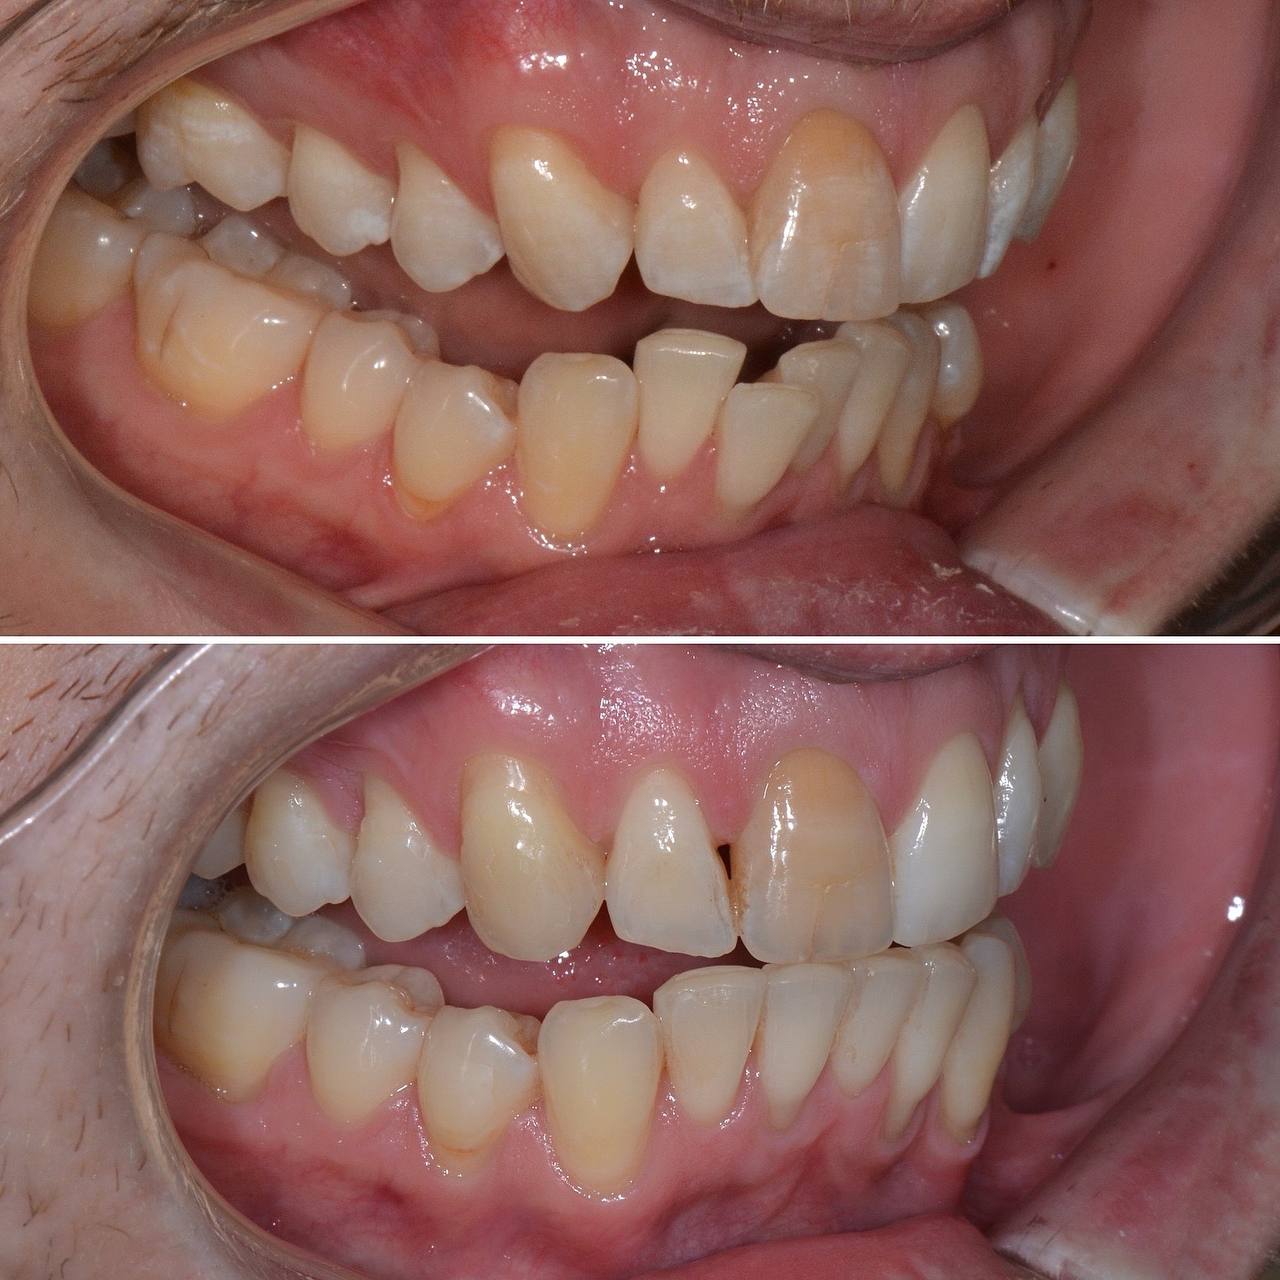

К нам с стоматологию обратился пациент с желанием сделать улыбку красивее. Лечением занимался стоматолог-ортодонт. Прикус и кривизну зубов исправляли при помощи элайнеров. Лечение заняло 12 месяцв. За это время было использовано 30 комплектов элайнеров.

Фото до и после лечения зубов элайнерами